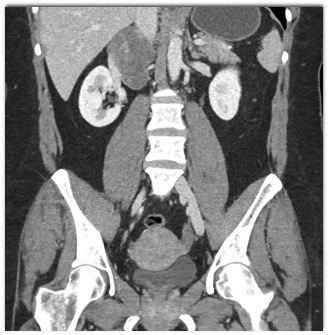

The best diagnosis in this case is

retroperitoneal liposarcoma

retroperitoneal myelolipoma

adrenal hemorrhage

adrenal myelolipoma